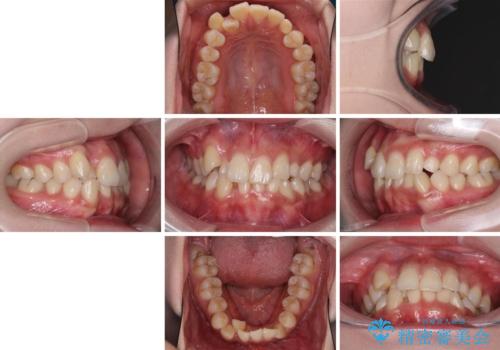

- 前歯のデコボコと残っている乳歯の部分へのインプラント治療を希望して来院された患者様です。

当初は目立たない上下裏側矯正を希望されていましたが、歯並びの悪さによる磨き残しが多く、歯肉炎が認められたため、より清潔な環境で治療を進められるインビザラインを選択することとしました。

前歯のデコボコが強かったため、上の奥歯を後方に動かす量が多くなり、結果として2年以上の治療期間を擁することとなりました。